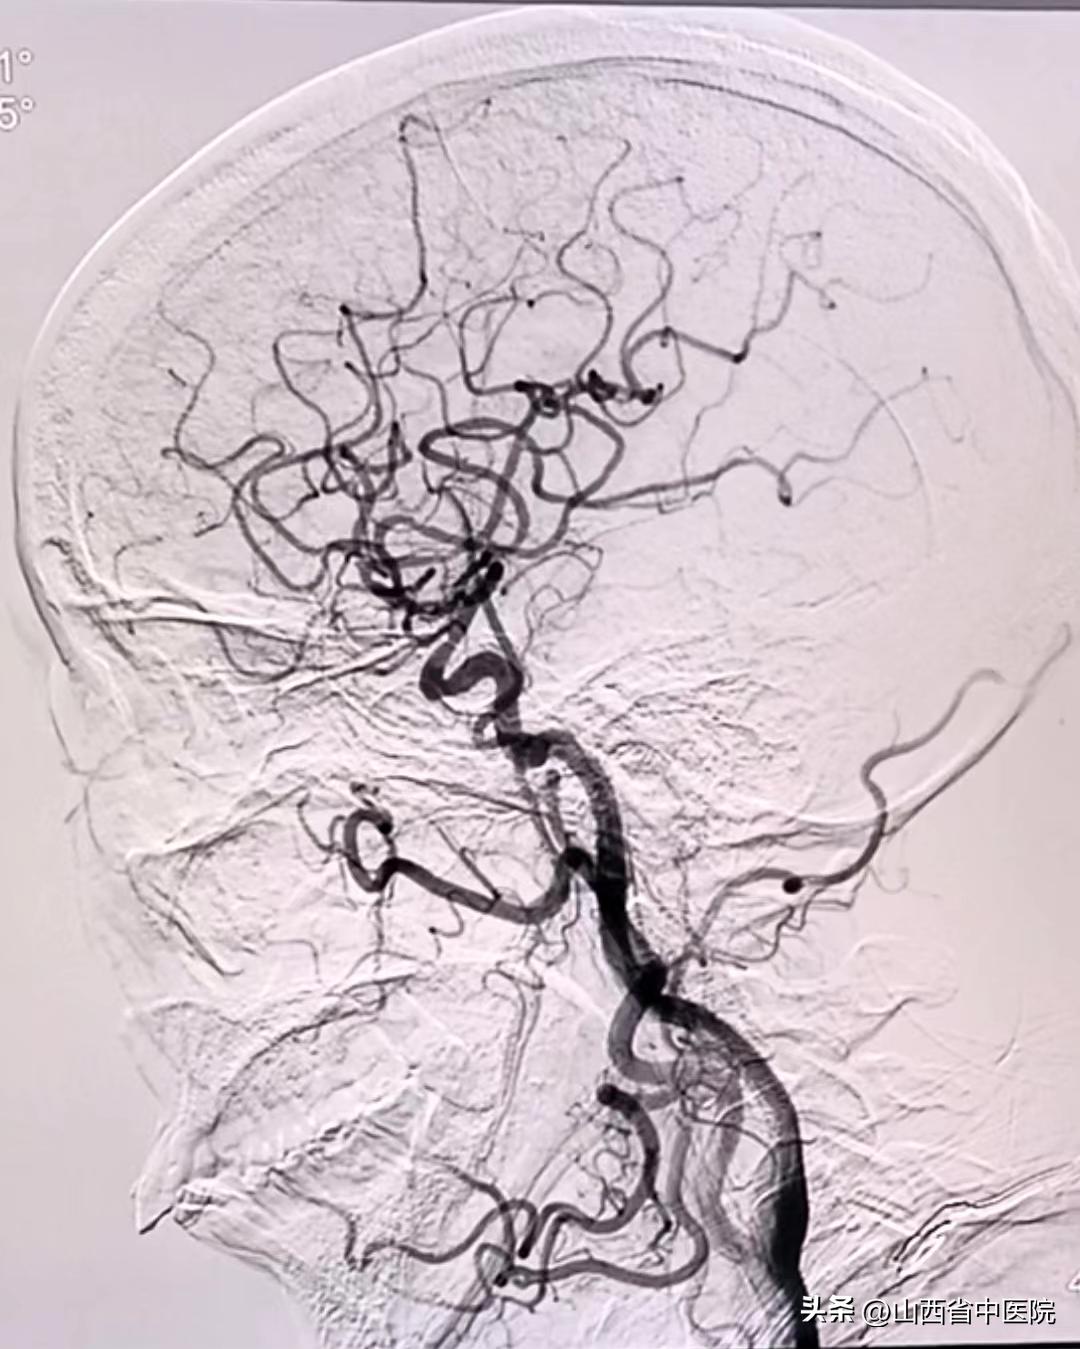

患者短时间内反复脑梗塞,肢体功能缺损严重,既往高血压病史30余年,2型糖尿病史5年余,如果真存在左侧大脑中动脉局限性狭窄,采取血管内治疗可能会帮助患者改善预后。经过科室讨论,决定为该患者进行了DSA检查明确病因。脑血管造影结果显示患者右侧大脑中动脉并未存在明显狭窄,左侧大脑中动脉纤细。因此,考虑患者脑梗塞原因为穿支病变,多次脑梗塞病因终于得以明确。随后经过规范的抗板降脂稳斑治疗,结合焦氏头针、经颅磁刺激治疗、药物扶阳罐及中药联合治疗,患者疗效显著。出院查体,患者下肢肌力恢复至4级,上肢3级,生活能够自理。